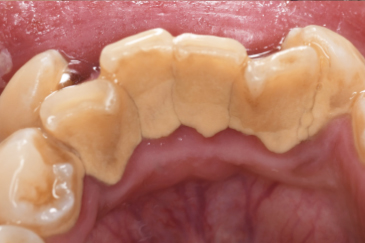

CASE 10

Before①

After①

Before②

After②

基本情報

| 年齢・性別 | 38歳・男性 |

| 主訴 | 下顎 歯石除去したい |

| 治療内容 | スケーリング |

| 治療期間 | 30分 |

| 治療費 | 約1,500円(保険診療) |

| リスク・副作用 | 知覚過敏、歯肉退縮 |

| 治療方針 | 歯肉縁上歯石を除去してから歯肉縁下歯石を除去します。ご自身でのプラークコントロールができるようになったら定期検診に移行します。 |

| 担当者所見 | 半年ぶりの歯科医院の受診。歯石が付きやすいためセルフケアの重要性をお伝えして、定期的にクリーニングを行います。出血率が高く炎症が強いため、今後はセルフケアを強化して歯周病治療を行います。 |